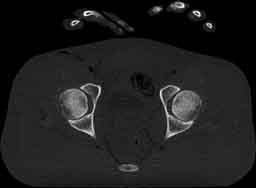

Visible Human male: Sectio transversalis 1873

CT

NMR

Pd                          / T2 \                         T1